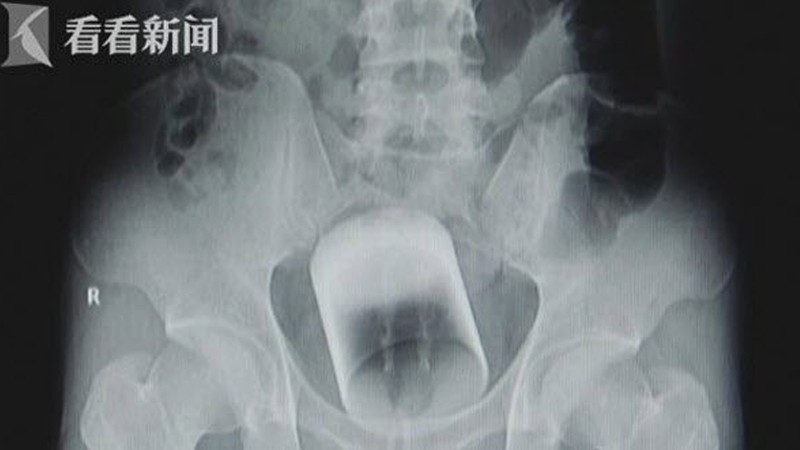

Өтгөн хаталтаас болж зовсон 60 настай хятад эрэгтэй шулуун гэдсээ туулгаар дүүргэхээр шийджээ. Тиймээс бүтэн лонх дүүрэн туулгыг шулуун гэдсэндээ хийсэн байна. Үр дүн нь ойлгомжтой.

Шулуун гэдсэндээ лонхтой туулга гацаасан эр эмнэлэгт хандсан аж. Аз болж эмч лонхыг аюулгүй салгасан боловч өвчтөний рентген зураг аль эрт цахим орчинд тархсан байжээ.